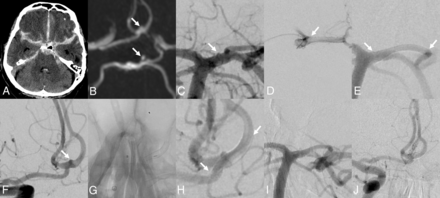

A, SAH primarily in the left Sylvian fissure on NCCT. The patient was Hunt and Hess 1 at that time, B, Aneurysm on the inferior trunk of the MCA, broad-based (white arrow). C, Implantation of a p48-MW-HPC flow-diverting stent from M1 into M2 (white arrows pointing to stent endings). D, DSA control 24 hours later. The flow diverter is patent; some stasis in the aneurysm is seen (white arrow). E, DSA control about 15 minutes later. Acute thrombosis developed on the superior trunk (white arrow). The flow diverter is patent. The patient had acute aphasia and hemiparesis after application of a pressure dressing in the groin. F, After therapy with IV tirofiban, the thrombosis disappeared (white arrow). The neurologic deficits resolved completely. G, After approximately 10 days, severe vasospam developed (white arrow). H, The vasospam, unfortunately, despite intense therapy, led to severe infarction of the left MCA and anterior cerebral artery territory (white arrow) (this is patient 9, Online Supplemental Data).

One patient (patient 9, Online Supplemental Data) with a broad-based berry-type aneurysm sitting asymmetrically on the inferior trunk of the left MCA right after the bifurcation was treated with a p48 MW HPC, applying regimen 1 (mentioned above under Materials and Methods). The patient initially was Hunt and Hess grade 1 and therefore clinically well, other than a significant headache, with no neurologic deficits. The procedure was performed successfully, and the patient awoke from anesthesia with still no neurologic deficits. A scheduled angiogram 24 hours after the procedure showed the flow diverter perfectly patent. However, after removal of the arterial sheath, groin compression and application of the pressure dressing, the patient suddenly developed an aphasia and a right hemiparesis up to an NIHSS of about 15 during about 10 minutes. In an immediately performed angiogram of the left internal carotid artery, a thrombosis of the overstented superior branch of the left MCA was noted, with the flow-diverting device being perfectly patent. A body weight–adapted bolus of tirofiban with consecutive body weight–adapted continuous infusion of tirofiban accompanied by an elevation of the mean arterial blood pressure was initiated; and the thrombus was resolved, and the hemiparesis and aphasia recovered completely. The patient was then switched to a dual-antiplatelet therapy with aspirin, 100 mg PO, and prasugrel, 10 mg PO. The patient remained stable under this therapy for about 10 days when he began to develop severe vasospasm in the left MCA territory, which was treated noninvasively as well as by an intra-arterial medical vasodilation treatment, but which finally led to significant infarction in the left MCA and anterior cerebral artery territory. The flow diverter remained patent throughout all of the controls. The reason for the initial acute thrombosis of the overstented superior trunk is not clear, but it was presumably due to a vaso-vagal reaction during the groin compression and a subsequent drop of blood pressure, which led to an overshoot of flow diversion and an initiation of the thrombosis in the superior trunk (Fig 2).